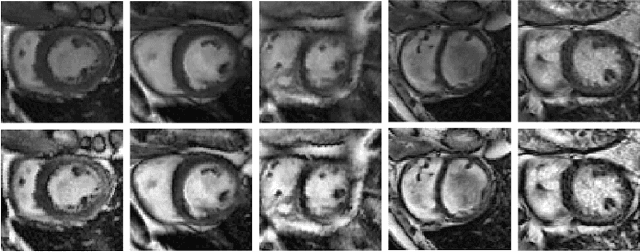

Quantitative assessment of cardiac left ventricle (LV) morphology is essential to assess cardiac function and improve the diagnosis of different cardiovascular diseases. In current clinical practice, LV quantification depends on the measurement of myocardial shape indices, which is usually achieved by manual contouring of the endo- and epicardial. However, this process subjected to inter and intra-observer variability, and it is a time-consuming and tedious task. In this paper, we propose a spatio-temporal multi-task learning approach to obtain a complete set of measurements quantifying cardiac LV morphology, regional-wall thickness (RWT), and additionally detecting the cardiac phase cycle (systole and diastole) for a given 3D Cine-magnetic resonance (MR) image sequence. We first segment cardiac LVs using an encoder-decoder network and then introduce a multitask framework to regress 11 LV indices and classify the cardiac phase, as parallel tasks during model optimization. The proposed deep learning model is based on the 3D spatio-temporal convolutions, which extract spatial and temporal features from MR images. We demonstrate the efficacy of the proposed method using cine-MR sequences of 145 subjects and comparing the performance with other state-of-the-art quantification methods. The proposed method obtained high prediction accuracy, with an average mean absolute error (MAE) of 129 $mm^2$, 1.23 $mm$, 1.76 $mm$, Pearson correlation coefficient (PCC) of 96.4%, 87.2%, and 97.5% for LV and myocardium (Myo) cavity regions, 6 RWTs, 3 LV dimensions, and an error rate of 9.0\% for phase classification. The experimental results highlight the robustness of the proposed method, despite varying degrees of cardiac morphology, image appearance, and low contrast in the cardiac MR sequences.